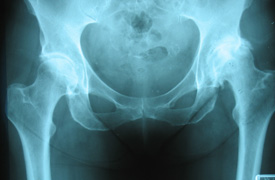

Hip resurfacing involves replacing damaged surfaces in the hip joint with metal surfaces. This procedure can be useful for patients under 65 with advanced hip disease

Hip resurfacing surgery is an alternative to standard hip replacements for patients with severe arthritis. In hip resurfacing surgery, the implant is smaller, and less normal bone is removed. Hip resurfacing is gaining interest, especially in younger patients

Hip Joint Replacement Surgery is usually considered once other therapies, such as pain medications, have failed. Most people undergo hip replacement as a result of osteoarthritis of the hip joint.